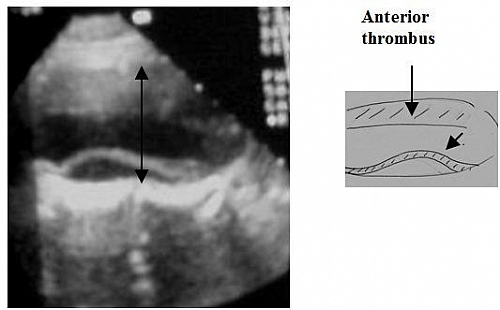

- Aortic aneurysm